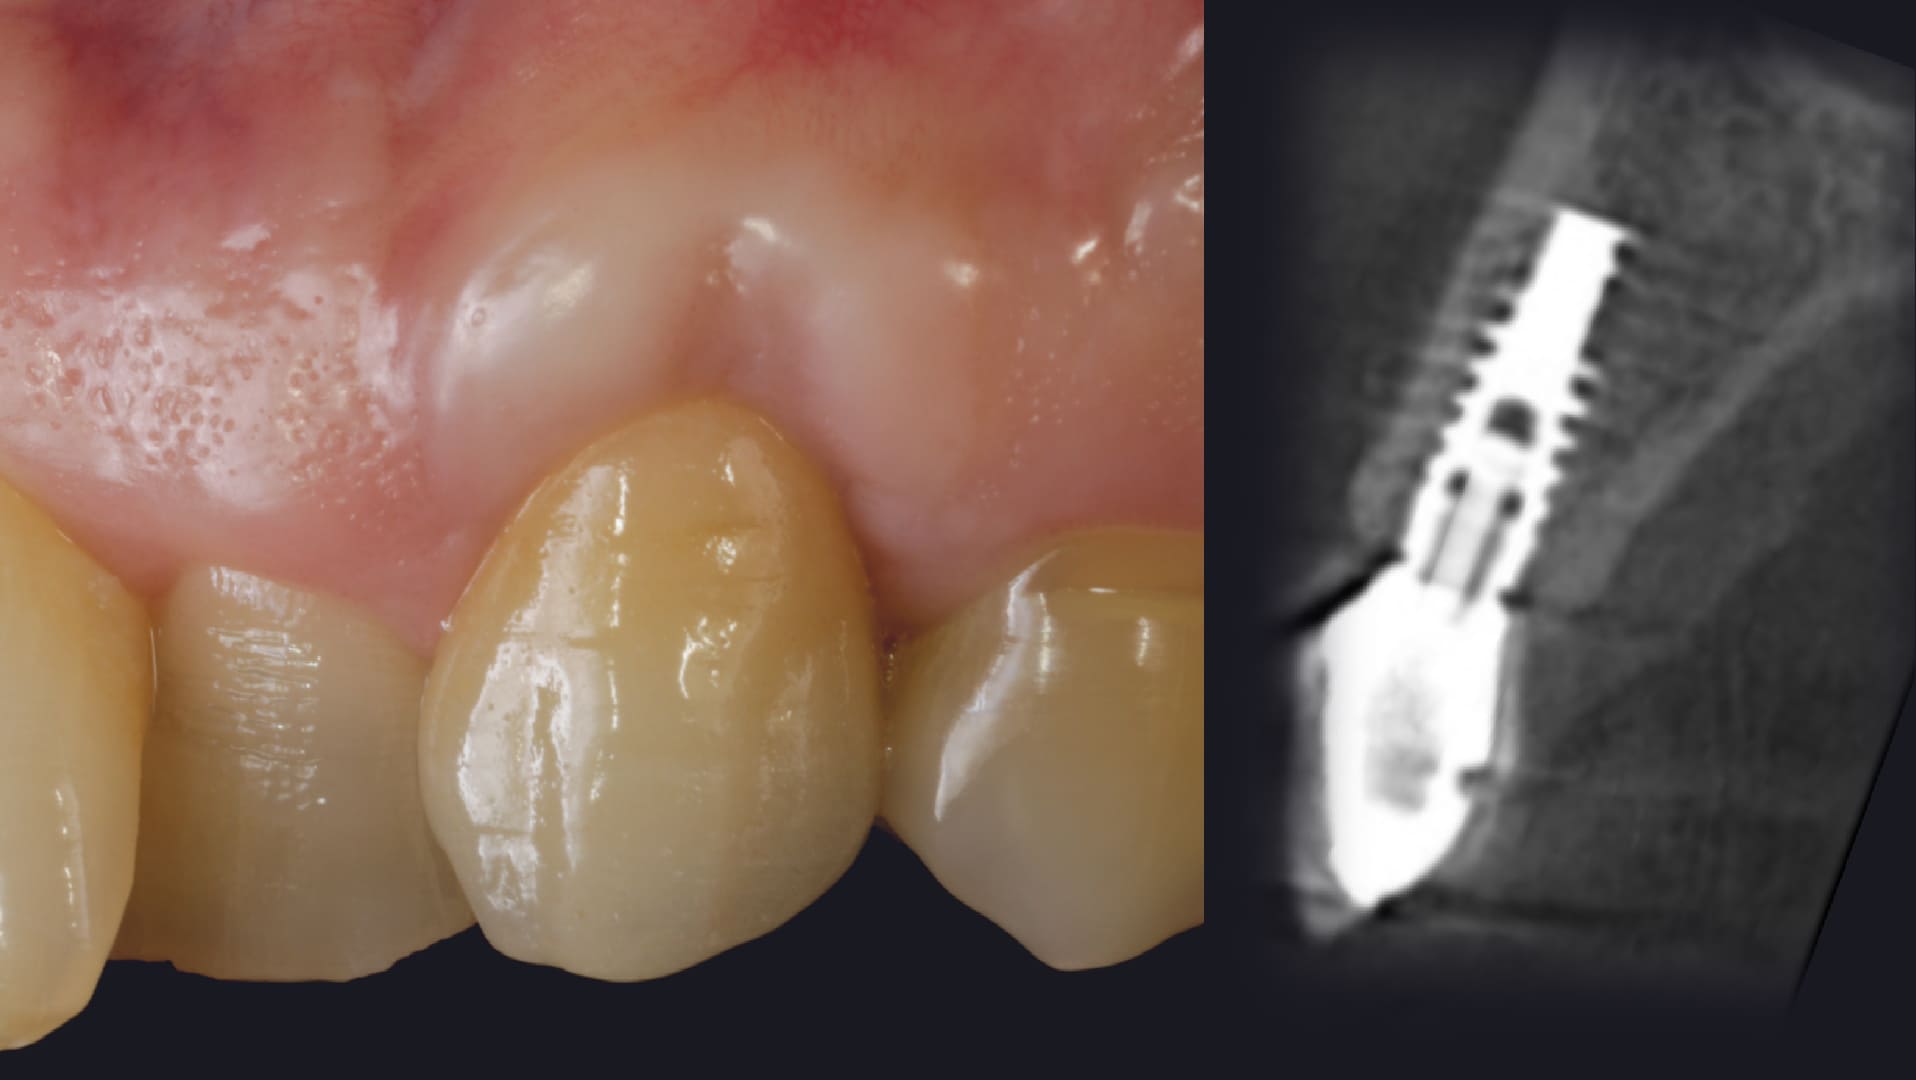

Management of the immediate provisional restorations contour

The importance of the Immediate Provisional Restorations.

Posterior Immediate Implants.